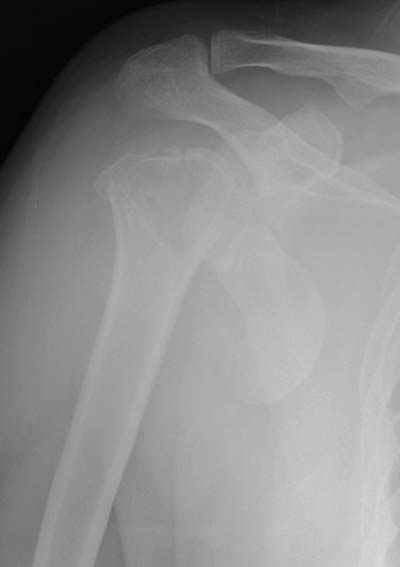

Женя, а как ты водишь спицы, в смысле, как делаешь входное отверстие, и как в него проводишь V-спицу? А то о дна из спиц, та, у которой не дошла до головки одна палочка буквы V, как-то выглядит на рентгенограмме, как будто или через очень большое отверстие введена, или каждая половинка через отдельные отверстия.

В чем ты видишь причину вторичного смещения?

Мне кажется, проблема в том, что не все концы спиц зашли в головку, и зашедшие - недостаточно далеко прошли.

Если наружной фиксации нет, то не понятно, как 4 спицы, проведенные в головку плечевой кости на 3-3.5 см удержат перелом от вторичного смещения.

Ведь, к сожалению, и после фиксации перелома шейки плеча пластинами различной конструкции,в полслеоперационном периоде иногда встречается вторичное смещение в переломе.